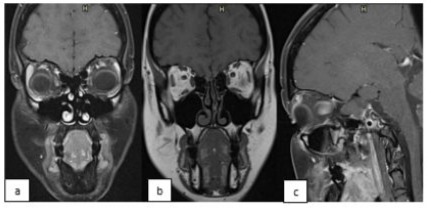

The patient was referred to the medical oncology department. After staging, local disease was diagnosed with no metastasis and she started with chemotherapy consisting of 4 cycles of ifosfamide, vincristine and actinomycin (IVA) according to Pediatric RMS regiment. After three IVA cycles, follow-up imaging magnetic resonance imaging (MRI) was evaluated which demonstrated diffuse orbital unresectable lesion. External Beam Radiotherapy (EBRT) was started with a total dose of 45 Gy, administered in 1.8 Gy doses, with continuation of the IVA chemotherapy treatment to 10 cycles in total. Good clinical and radiologically response was noted with reduction in lid swelling, conjunctival redness and radiologically stable residual imaging enhancement over a long follow-up period of 13 years with full remission. (Figure 2) At last, follow up visit (13 years) ophthalmological evaluation showed; BCVA 0.8 (at tumor side), mild dry eye according to Schirmer test evaluation, facial asymmetry due to left enophthalmos and upper eyelid hollowness, and left eye elevation limitation due to inferior oblique muscle paresis. The main patient complaints are facial asymmetry with esthetical complaints, double vision (solved by prisms) and mild photophobia due to dry eyes. The patient was treated with local lubricants and planned for reconstructive orbital surgery with 3D printed implant and fat graft injection to fix the asymmetric enophthalmos matter.

Figure 2: MRI, Coronal T1(a), Coronal T2(b) and Sagittal sections, at last follow up showing minimal residual enhancement and minimal orbital asymmetry.